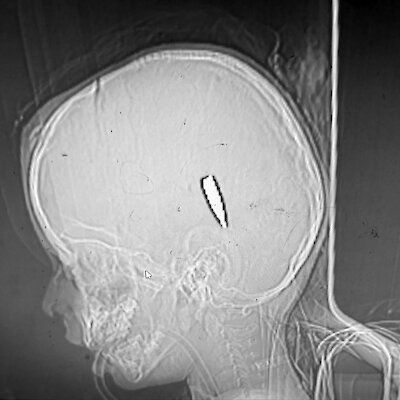

Использование осколочных боеприпасов

Девять врач:инь сообщили журналист:кам, что сталкивались с ранениями у детей, вызванными крошечными металлическими осколками кубической или цилиндрической формы размером всего в несколько миллиметров.

Такие осколки особенно опасны: раны могут казаться незначительными на первый взгляд, но впоследствии приводят к повреждениям органов, нервов, кровеносных сосудов, внутреннему кровотечению и так далее. В таких боеприпасах зачастую используется вольфрам, который и был обнаружен в ранениях. Это чрезвычайно твердый и тяжелый металл, наносящий еще больший урон при взрыве боеприпаса.

Хирург Марк Перлмуттер утверждает, что оперировал по меньшей мере десять человек с такими осколками и смог тайно вывезти два фрагмента из сектора Газа, передав их в Международный уголовный суд.